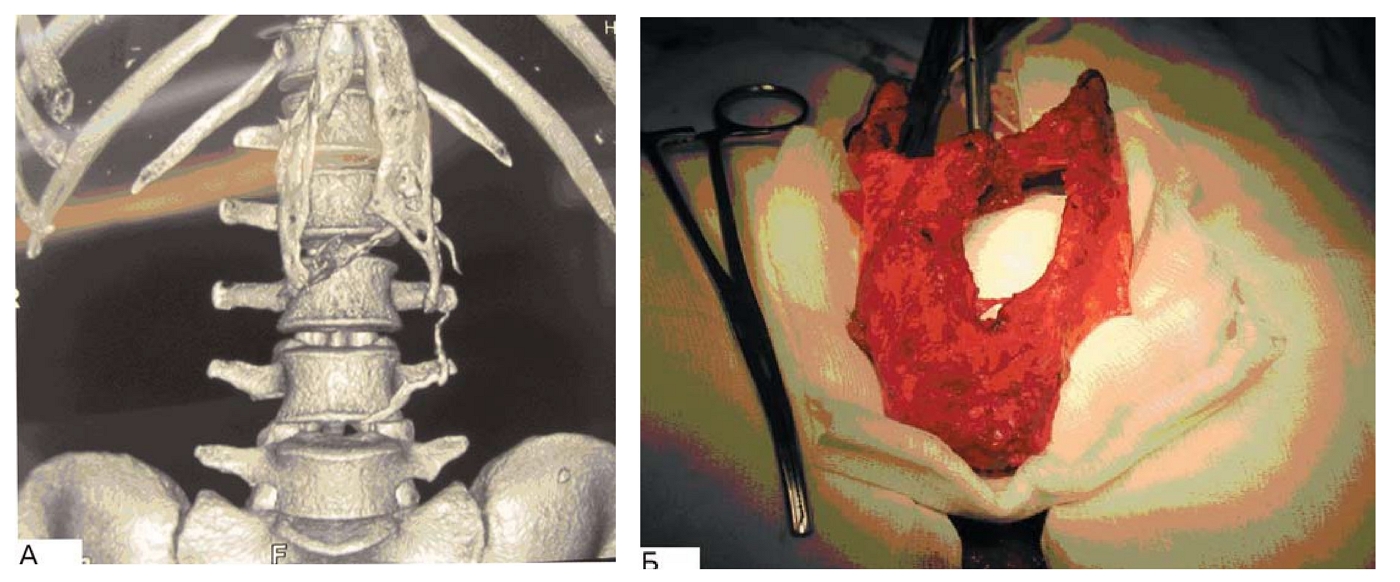

При выполнении санационных релапаротомий мы накладываем швы только на кожу с подкожно-жировой клетчаткой, что улучшает вентиляционные функции легких, позволяет избежать прорезывания швов апоневроза, а последующая операция по устранению послеоперационной грыжи намного проще в техническом исполнении, чем при деформированном с прорезанными краями апоневрозе [7]. Неоднократные санационные релапаротомии могут приводить к образованию хрящевидной ткани (оссификатов) по краям раны, что, вероятно, обусловлено контактом токсического выпота из брюшной полости с мягкими тканями передней брюшной стенки (рис. 6).

Рис. 6. Компьютерная томограмма: образование оссификатов по периметру апоневроза (А), макропрепарат иссеченного. оссификата (Б).